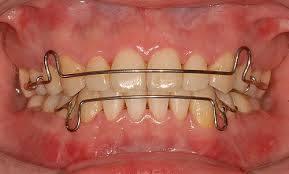

②Hewley's retainer(沒啥固定中文譯名,有人叫哈雷維持器,有人叫有鐵絲的那種維持器,有人叫活動式維持器....)

Hewley's retainer

哈雷維持器

最傳統好用的維持器,有多種設計變型。我當初做完矯正,就是用此種維持器,只是如缺點所言,我戴了3個月就不戴了,下前牙就小跑位了,還好我自己能接受(這時很多人就會天人交戰,to be or not to be,要不要再來二次矯正?)。

優點:因為有粗的矯正鋼線,所以維持性最好,有因咬合面

開放,不容易被咬壞,可以用個好幾年都沒問題,很

耐用。不過這也是問題,用久了,維持器的鐵線難免會

變形,需要進廠(診所)維修一下。《我的矯正病人通常

我會請其在定檢洗牙時,順便帶回來讓我微調一下。》

缺點:就是量體較大,異物感較明顯,需學習一段適應期間,

通常一兩週。尤其戴過①透明維持器的病人。

哈雷維持器(口內照)